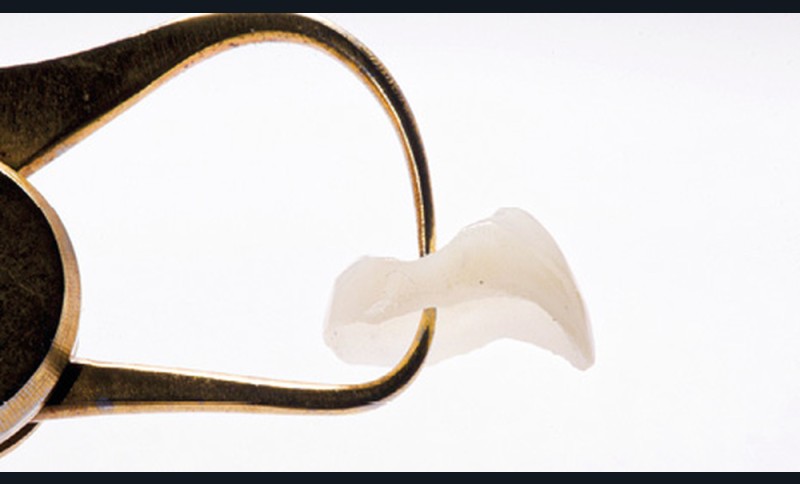

La pièce prothétique est dessinée sur un logiciel de modélisation dentaire, puis elle est imprimée en résine calcinable et transformée en céramique (disilicate de lithium) par technique pressée (fig. 14).